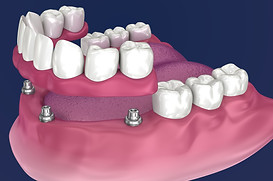

Zygomatic implants are a game-changer for patients with severe bone loss, but mastering this advanced technique requires specialized training. With so many courses available globally, choosing the right one can be challenging.